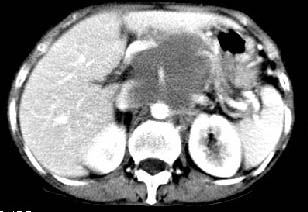

胰腺受压前移,胰管扩张,应为腹膜后占位,病灶密度不均,有低密度坏死区,强化扫描强化不明显腹腔干动脉受侵,考虑腹膜后恶性占位

从发病部位(腹主动脉周围)及增强方式(均匀轻度强化、少量坏死)和病变形态(较大、多结节形)符合腹膜后淋巴瘤,建议颈部病变活检。

我的第1诊断还是考虑是淋巴类病变1}。从病灶形态上看不是很规则,但其更向是多个结节的融和,其内有少许坏死,整个病灶的强化不是很明显,临近左恻肠间隔有增厚,2}我认为更重要的一点的是肠系膜有明显增厚呈片状。3}患者的脾脏不大其未见异常病灶。结合以上几点我首先考虑是转移性{但对此诊断我觉得不足之处;转移性的淋巴结肿大融合为什么没有坏死?}。{另外患者无大便习惯改变及血便,其发现右颈包块在今年过年无意发现}。以上是我的浅分析望各位战友继续讨论!谢谢!!

肝胃之间、肝十二指肠韧带,胰头后、腹主a周围,融合而成团块状影,包绕血管[腹腔干、肠系膜上动脉,腹主动脉],胰腺前移后缘分界欠清,与肝胃分界清,肿块未见明显强化,肝右叶后段小囊肿。

主动脉-胰腺间隙可见巨大分叶状软组织肿块影,包绕腹主动脉、腹腔干及其分支、腔静脉等大血管,增强呈无明显强化,临近脏器明显受压移位,增强示有分界。肝右叶可见局限性低密影,边缘清楚。